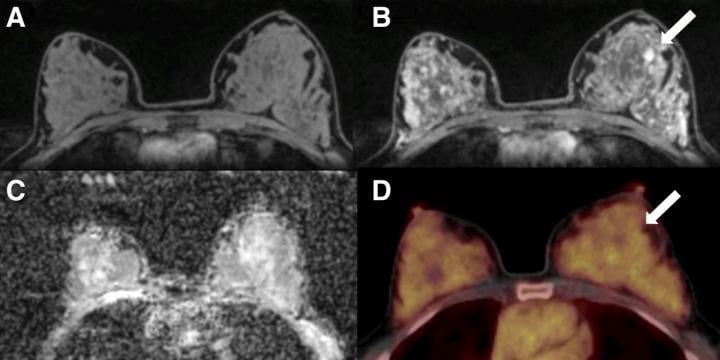

A 50-y-old postmenopausal woman with fibroadenoma (arrows) in left breast. (A) Unenhanced fat-saturated T1-weighted MRI shows extreme amount of FGT (ACR d). (B) Moderate BPE is seen on dynamic contrast-enhanced MRI at 90 s. (C) Mean ADC of breast parenchyma of contralateral breast on diffusion-weighted imaging with ADC mapping is 1.5 × 10?3 mm2/s. (D) On 18F-FDG PET/CT, lesion is not 18F-FDG-avid, and BPU of normal breast parenchyma is relatively high, with SUVmax of 3.2. Photo courtesy of K Pinker, et al., Medical University of Vienna, Vienna, Austria

The study included 141 patients with imaging abnormalities on mammography or sonography on a tumor-free contralateral breast. The patients underwent combined PET/MRI of the breast with dynamic contrast-enhanced MRI, diffusion-weighted imaging (DWI) and the radiotracer 18F-FDG. In all patients, several imaging biomarkers were recorded in the tumor-free breast: background parenchymal enhancement and fibroglandular tissue (from MRI), mean apparent diffusion coefficient (from DWI) and breast parenchymal uptake (from 18F-FDG PET). Differences among the biomarkers were analyzed by two independent readers.

A total of 100 malignant and 41 benign lesions were assessed. In the contralateral breast tissue, background parenchymal enhancement and breast parenchymal uptake were decreased and differed significantly between patients with benign and malignant lesions. The difference in fibroglandular tissue approached but did not reach significance, and the mean apparent diffusion coefficient did not differ between the groups.

"Based on these results, tracer uptake of normal breast parenchyma in 18F-FDG PET might serve as another important, easily quantifiable imaging biomarker in breast cancer, similar to breast density in mammography and background parenchymal enhancement in MRI," Leithner explained. "As hybrid PET/MRI scanners are increasingly being used in clinical practice, they can simultaneously assess and monitor multiple imaging biomarkers--including breast parenchymal uptake--which could consequently contribute to risk-adapted screening and guide risk-reduction strategies."